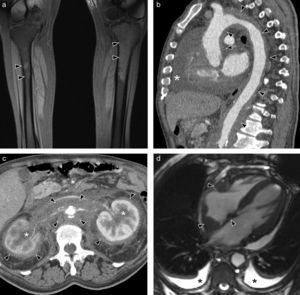

Erdheim-Chester's syndromeErdheim-Chester's syndrome is a rare systemic disease, which anatomopathologically corresponds to a histiocytosis of non-Langerhans cell. It may present various signs depending on the organs affected: osseous affection is practically constant (long bone metaphysodiaphysary and extraskeletal osteosclerosis (Fig. 10a)), occurs in almost half the patients, including retroperitoneal infiltration, cardiovascular affection, as well as that of the central nervous system, exophthalmos and interstitial pulmonary diseases. In the image tests, when the aorta is affected, periaortic tissue is infiltrated circumferentially from the ascending aorta to the iliac bifurcation (image of “coated aorta”) (Fig. 10b and c). This infiltrate is hypointense in the adjusted echo spin MR sequences on T1 and T2 (Fig. 10d).32,33

Erdheim-Chester's syndrome of a 66-year-old man with chronic thoracic pain and toxic manifestations. (a) MR coronal image of lower limbs (sequence T1 with fat saturation) showing a signal alteration in the left tibia upper third and patched affectation of right tibia upper diaphysis (arrow heads). (b) Sagittal MPR reconstruction of CT with contrast. Extensive periaortic thickening with vascular wall irregularity (arrow heads), from the aortic root to the abdominal aorta. Abundant pericardial effusion (asterisk). (c) Axial CT image with contrast showing hypodense tissue infiltrating periaortic and perirrenal regions (arrow heads), with compromise of renal hili and secondary bilateral hydronephrosis (asterisks). (d) MR axial image in 4 heart chambers (cine gradient sequence) showing hypointense tissue around the right auricle, interauricular septum and right coronary artery (arrow heads). Small bilateral pleural effusion (asterisks).